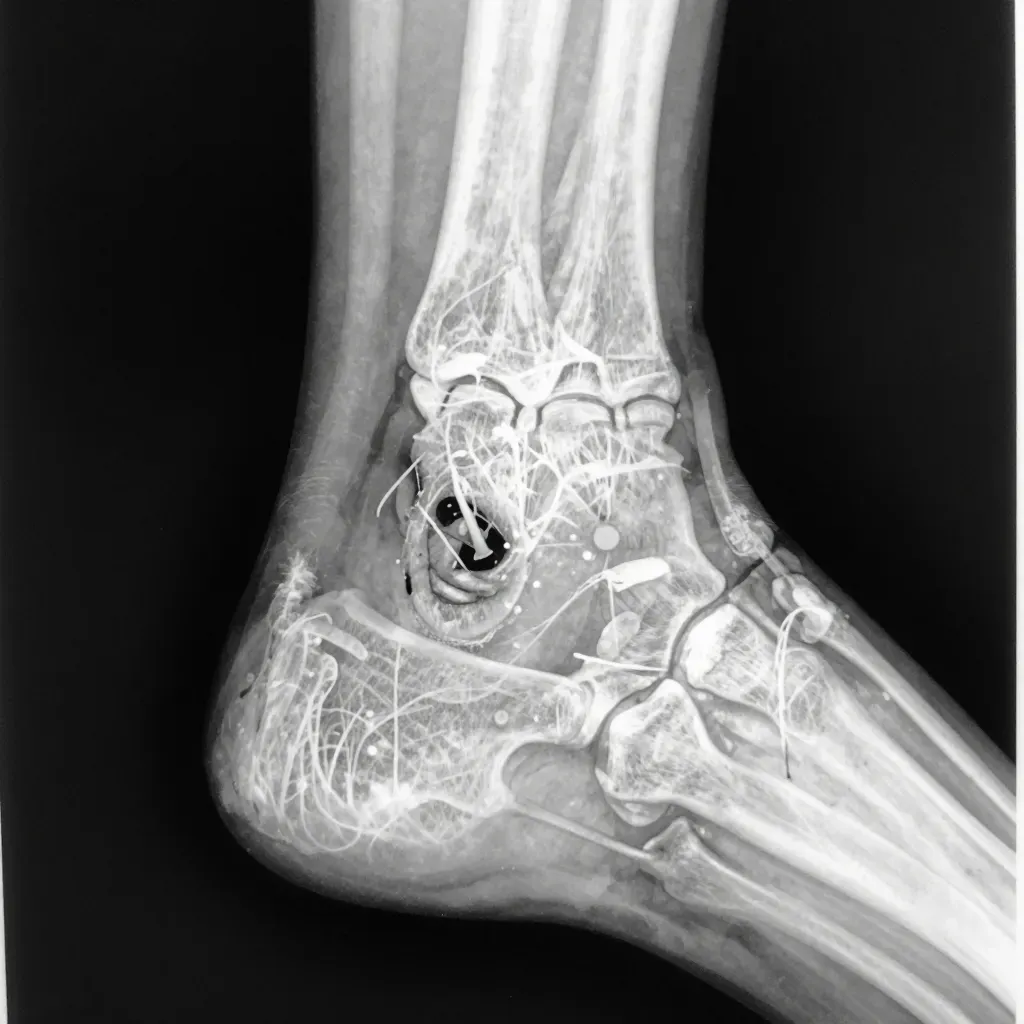

What an x ray can reveal about toenail infections

X rays show more than just bone. They reveal the full picture of what an ingrown toenail infection hides beneath the skin.

Bone involvement

Osteomyelitis shows up as dark spots or holes in the bone. The toe bone may look rough or irregular instead of smooth. These changes mean bacteria attacked the bone structure.

Chronic infections cause the bone to thicken. Doctors call this sclerosis. The body tries to wall off the infection by building denser bone around it.

Soft tissue changes

- Swelling patterns show infection spread

- Gas bubbles in tissue indicate serious bacterial infection

- Thickened nail bed suggests chronic inflammation

- Fluid collections point to abscess formation

Joint damage

The big toe joint sits close to ingrown nail sites. Infection can seep into the joint space. X rays show narrowed joint spaces or eroded cartilage. Joint infections require immediate treatment to prevent permanent stiffness.